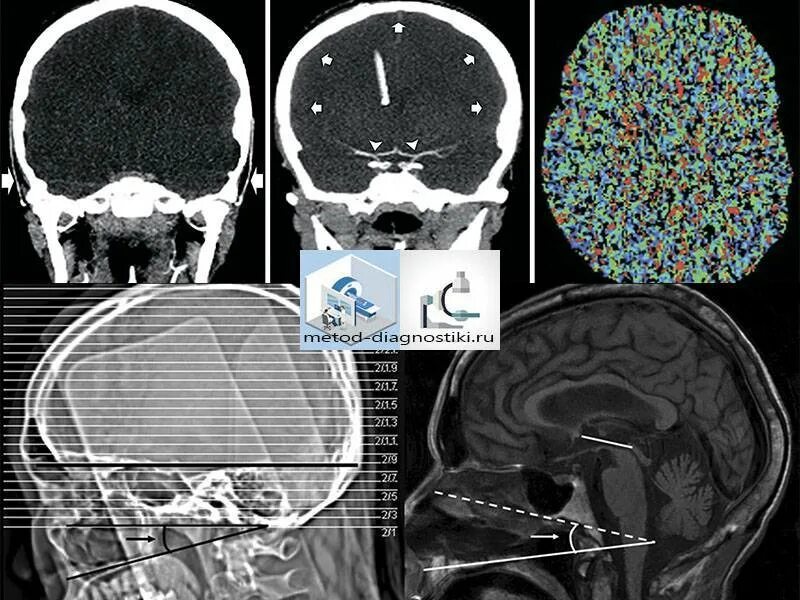

Рентген и мрт в чем разница